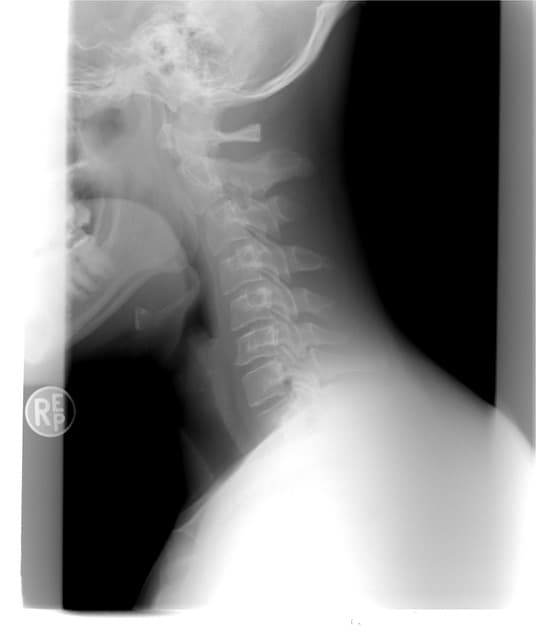

갑상선 목부음

주변을 둘러보면 갑상선에 대한 질병을 흔하게들 많이 들어보셨거나 볼 수 있으실거에요. 한편 갑상선은 우리 목에 위치해 있는데요. 한편 신진대사에 필요한 갑상선 호르몬을 분비하는 내분비기관을 말하는 것으로 전해지고 있는 것으로 파악되고 있습니다.

각종 대사에 필요한 호르몬이기 때문에 갑상선은 매우 중요하죠. 한편 하지만 갑상선 목부음 증상을 느끼시는 분들이 많이 계실텐데요. 더불어 세포성장이 과하게 이루어지거나 할때 갑상선에 종양이 생겨서 갑상선 목부음이나 이물감을 느낄 수 있는 것으로 파악되고 있습니다. 갑상선에 불편함을 느끼고 종양이 생기는 것은 전세계적으로 약 5%정도 가지고 있다고 하는 것으로 알려져 있는 것으로 보여요. 한편 개개인에 따라 갑상선이 위치도 다르고 개수나 크기도 다르고 갑상선 목부음 증상도 다르게 나타난다고 하는 것으로 알려져 있는 것으로 보여요. 갑상선 목부음은 갑상선종으로 불리우는데요. 한편 이게 크기가 커지거나 통증이 심해지면 숨을 쉬거나 음식을 삼키는데 불편함이 생겨 일상생활속에서 많은 불편함을 느낄 수 있다고 하는 것으